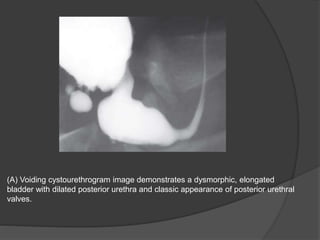

(A) Voiding cystourethrogram image demonstrates a dysmorphic, elongated

bladder with dilated posterior urethra and classic appearance of posterior urethral

valves.

(B) Dilating vesicoureteral reflux is

seen bilaterally.